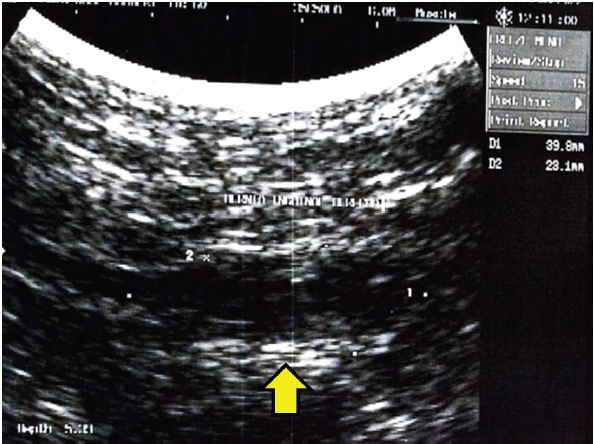

Hallazgos imagenológicos: el ultrasonido de piel y partes blandas reportó protrusión de asa intestinal a través del anillo inguinal superficial derecho, posterior a maniobras de Valsalva (Fig. 1).

Fig. 1 Ultrasonido de piel y partes blandas de región inguinal derecha. Se utilizó un transductor de 6.0 Megahercios multifrecuencia. Se evidenció imagen hipoecoica de 4,0 cm x 2,3 cm.